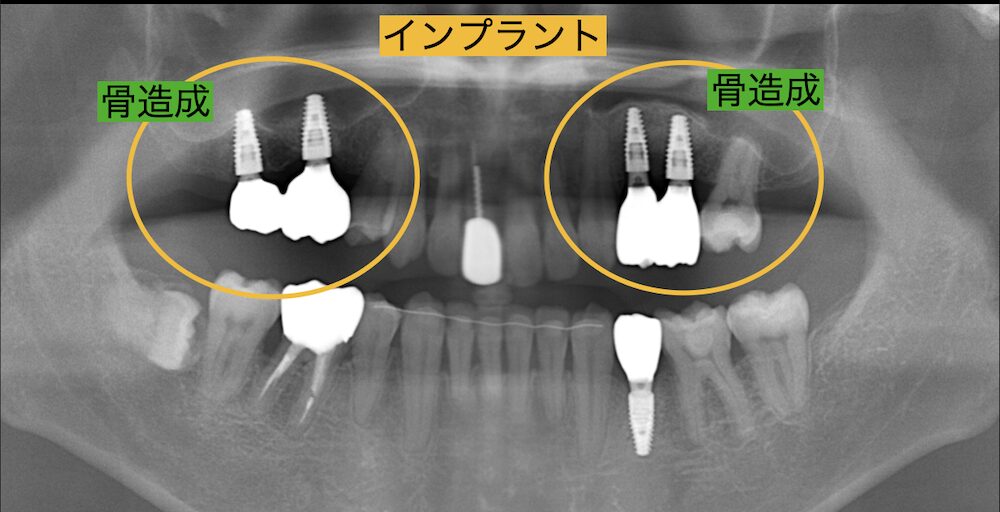

そこで意を決して治療に来られました。インプラントをするには骨が少なかったので骨造成を行い、無事にインプラントを入れることができました。

それからは奥歯でしっかりと噛めるようになったので、胃腸の調子も改善し体調がとても良くなったと喜ばれました。